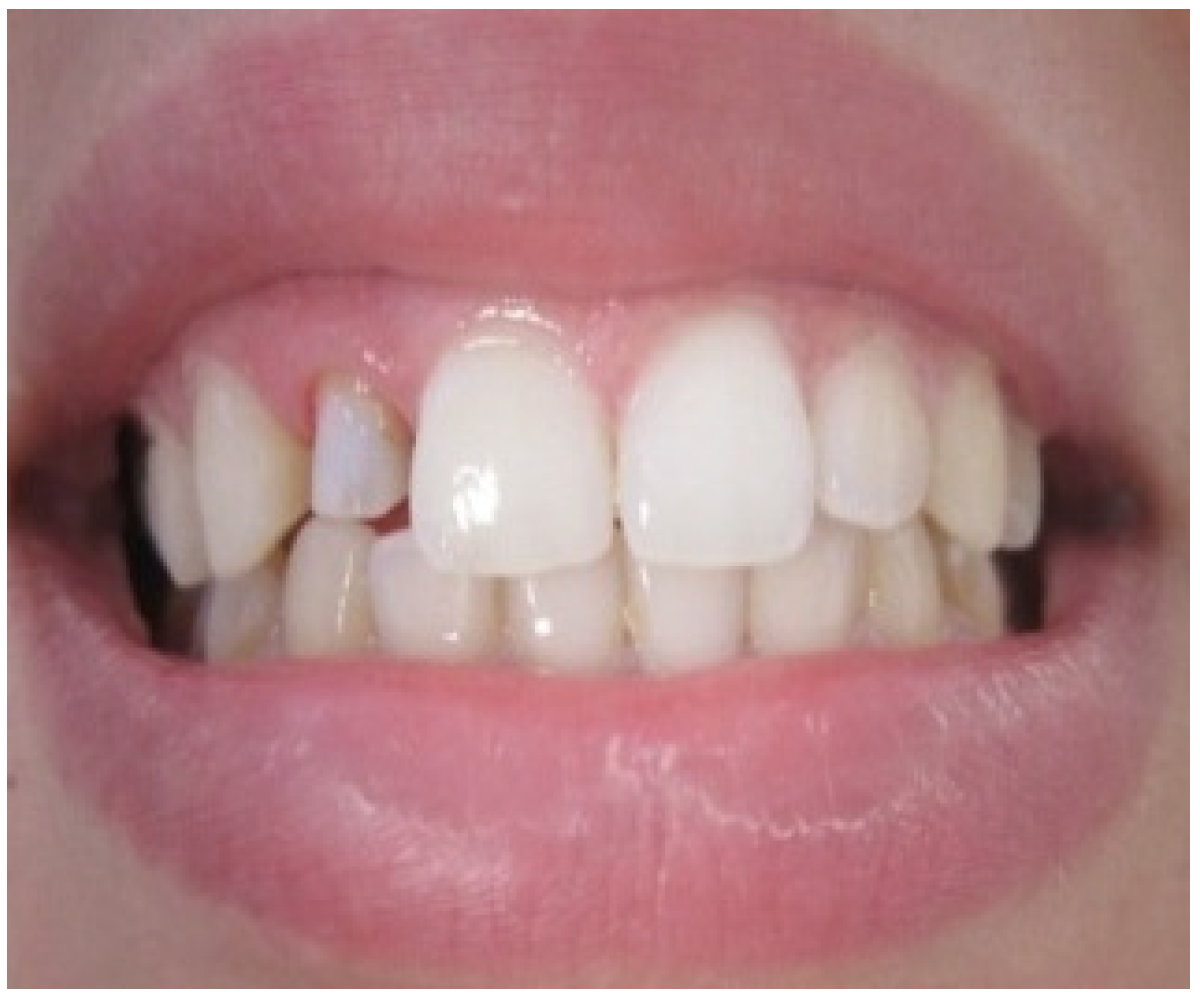

Aesthetic assessment showed a squared teeth form, a size discrepancy and a non-symmetrical gingival architecture between the left and right lateral incisors (Figure 2). A slight asymmetry between the gingival margins of the right and left central incisors was noticeable. However, the patient did not express her dissatisfaction about it and refused any surgery on her sound teeth.

Gingival zenith was evaluated as non-aesthetic as it occupies a location that does not coincide with the long axis of the tooth.

Figure 2. Gingival display due to the asymmetrical ZENITH.